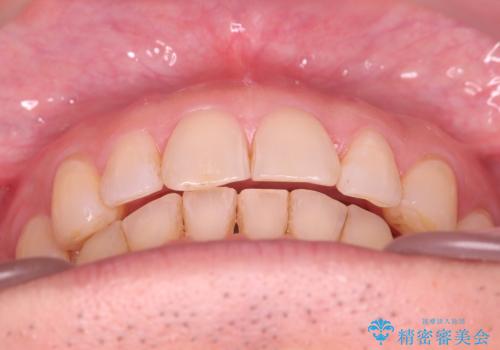

【インザライン】前歯の凸凹を治したい

- 前歯の凸凹を主訴に来院されました。

下顎位が右方に変異しており、外科矯正も提案しましたが患者様は希望されず、インビザラインにて治療を完了しております。

叢生のスペースを確保するために、臼歯部の遠心移動を行っています。

今回の治療計画は上顎の正中を顔と揃えることを優先しています。